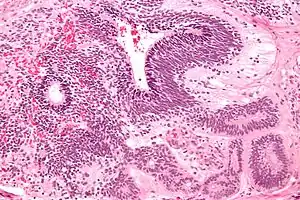

A micrograph of the primitive neuroepithelium of an immature teratoma, showing encapsulated mass.[6]

Teratoma are most common germ cell tumor of ovary. Teratomas can be divided into two types: mature teratoma (benign) and immature teratoma (malignant). Immature teratomas contain immature or embryonic tissue which significantly differentiates them from mature teratomas as they carry dermoid cysts.[7] It is commonly observed in 15 to 19-year-old women and rarely in women after menopause.[8] Immature teratomas are characterized with a diameter of 14–25 cm, encapsulated mass, cystic areas, and occasional appearance of hemorrhagic areas.[9] The stage of immature teratomas is determined depending on the amount of immature neuroepithelium tissue detected.[7]